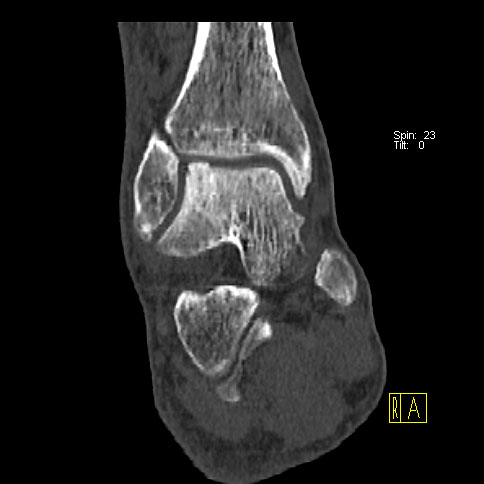

Die Kombination von SPECT und CT in einem Untersuchungsgang bringt wie bereits oben erwähnt eine erhöhte Ortsauflösung und artefaktfreie Darstellung von Knochenstoffwechselveränderungen der SPECT bei gleichzeitig excellent guter anatomischer Darstellung/Zuordnung durch die CT 3. Auf die Vorteile der CT gegenüber dem konventionellen Röntgen muss nicht mehr besonders eingegangen werden. Besonders eignet sich die „SPECT-CT“ zur Diagnostik von Fußerkrankungen (Biersack HJ et al. 2012).